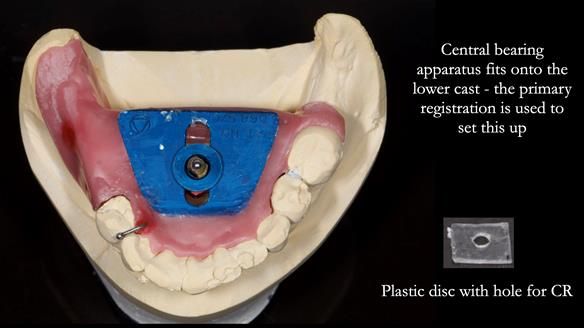

Welcome to my Newsletter 54 showing the making and fitting of dentures (a complete upper metal reinforced denture, a lower immediate partial denture and a definitive Scandinavian designed, metal based lower partial denture) for David, a 75 -year-old man. The full protocol workflow is presented including the use of dentate photographs to mimic his natural teeth.

The clinical situation and treatment process is shown in detail below. I provided the clinical work. Rowan Garstang, my dental technician, provided the technical work.

Interestingly we found that the upper complete denture when finished and fitted didn’t have good enough retention for David’s satisfaction. It was relined by adding compound to the buccal flanges – to almost overextend into the sulcus to ‘create’ a sulcus, followed by using a light bodied silicone impression material. This improved the function of the C/-considerably. A lower Scandinavian hygienically designed lower RPD was also provided which helped with occlusal stability and reseating the upper denture – further improving the fit.